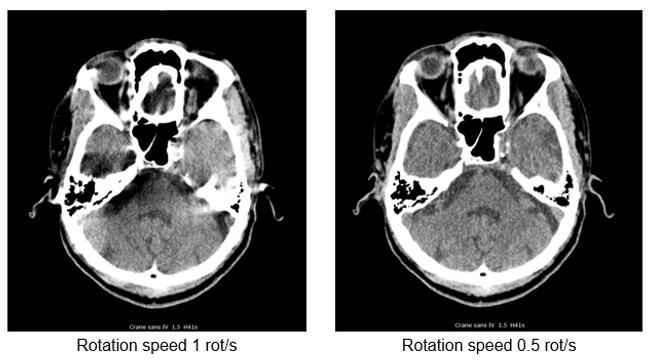

Temporal resolution is an indication of a CT system’s ability to freeze motions of the scanned object. Several factors influence the temporal resolution. The key factors are the gantry rotation time, acquisition mode, type of image reconstruction, and the pitch.

- The rotation speed is the time in seconds required for the tube to achieve 1 complete rotation (360°) and acquire its raw data

- Used for the skull and the lumbar spine. It is avoided for thorax-abdomen and heart scanner exams requiring long time apnea

- To avoid image degradation caused by the patient movements (artifacts) and involuntary movements (peristalsis and heartbeats)

Faster scanners have improved motion as the patient has less time to move during the scan. This can be accomplished with faster gantry rotation or more x-ray sources. Compare these two images for motion. The image on the right has a much better resolution than the one on the left.